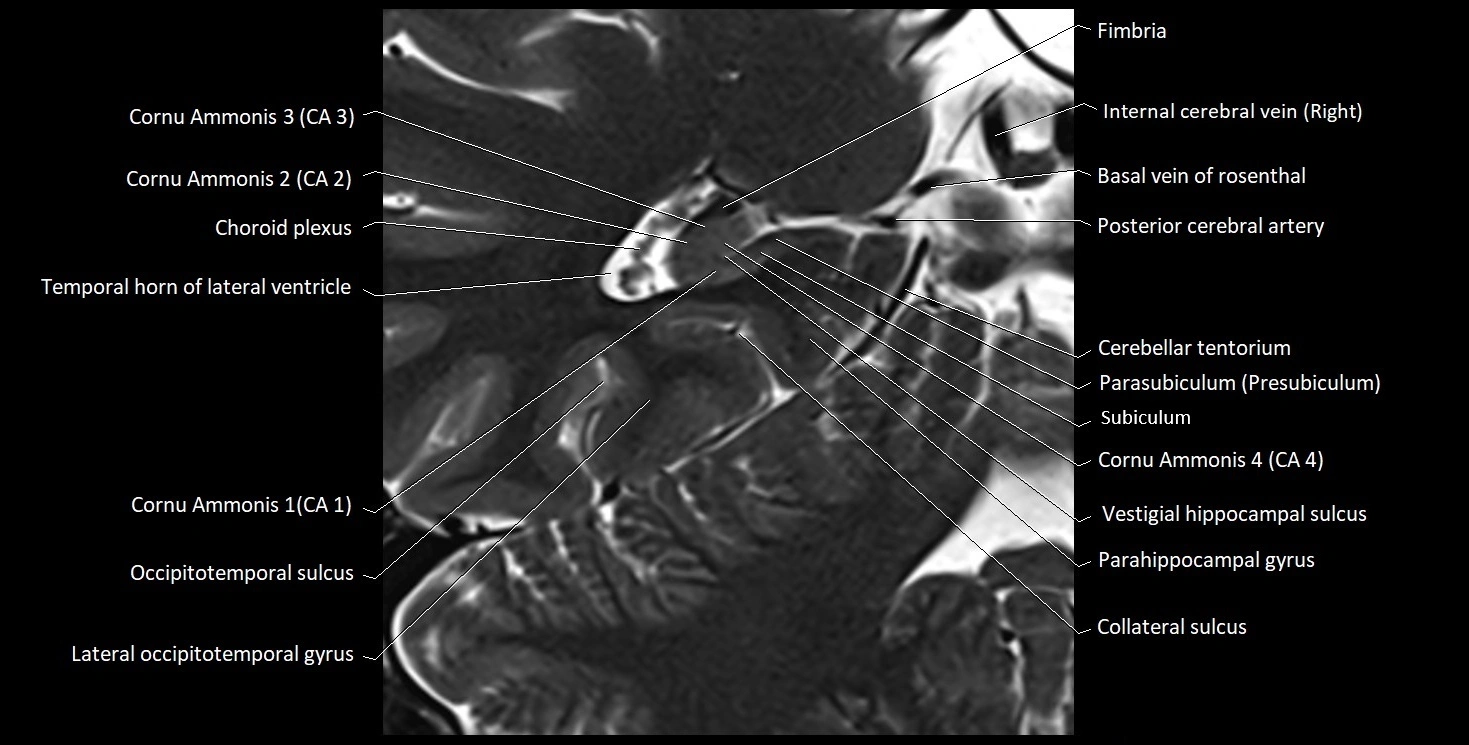

The alveus of the hippocampus is a thin, white matter layer covering the superior (ventricular) surface of the hippocampus within the temporal horn of the lateral ventricle. It consists of myelinated efferent fibers arising primarily from the pyramidal neurons of the hippocampus. These fibers converge medially to form the fimbria of the hippocampus, which continues posteriorly into the fornix, forming a crucial part of the Papez circuit involved in memory consolidation and emotional processing.

The alveus serves as the initial output pathway of the hippocampal formation, linking it to other limbic structures including the hypothalamus, mammillary bodies, and cingulate gyrus. Because of its intimate relationship with the hippocampal head and tail, it is often evaluated in cases of temporal lobe epilepsy, hippocampal sclerosis, and neurodegenerative diseases.

Location and Structure

• Position: Lies on the ventricular (superior) surface of the hippocampus, beneath the ependyma of the inferior horn of the lateral ventricle.

• Composition: A thin sheet of myelinated axons derived mainly from hippocampal pyramidal cells.

• Course: Fibers run medially along the hippocampal surface to form the fimbria of the hippocampus, which curves upward and backward into the fornix.

• Relations:

• Superiorly: Ependyma and CSF of the temporal horn of the lateral ventricle

• Inferiorly: Pyramidal cell layer of the hippocampus (CA1 region)

• Medially: Fimbria and fornix

• Laterally: Temporal lobe white matter and parahippocampal gyrus

MRI Appearance

T2-weighted images:

• Alveus: Low signal line overlying brighter hippocampal gray matter.

• CSF: Bright hyperintense.